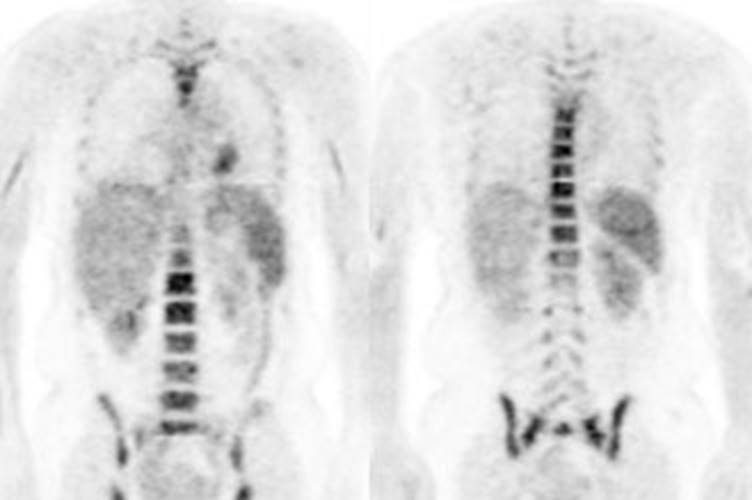

Figure 21 - Marrow activity: The images below are from

two separate patients each showing mild FDG accumulation within the vertebral

bodies.

Figure 22 - Growth colony effect: The patient shown below

had received growth colony stimulating factor (GCSF). Note the extensive

increased marrow activity. Note increased splenic activity also seen as a result of GCSF therapy.